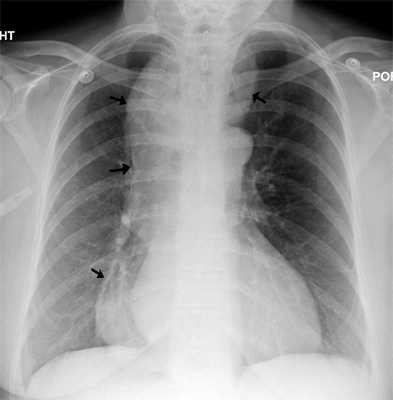

Примерно у половины пациентов рентгенологическое исследование не выявляет признаков патологии. На эзофагоспазм указывают некоординированные спастические сокращения мышц пищевода, из-за чего орган приобретает вид штопора, четок, псевдодивертикулов. Контрастная эзофагография при спазме верхнего сужения пищевода демонстрирует задержку контраста на уровне перстневидного хряща. При хроническом спазме контраст скапливается в области супрастенотического расширения. Для синдрома Баршоня-Тешендорфа характерно выявление кольцевидных спазмированных участков на всем протяжении пищевода. От ахалазии кардии спазм пищевода отличается нормальным прохождением контраста через нижний пищеводный сфинктер.